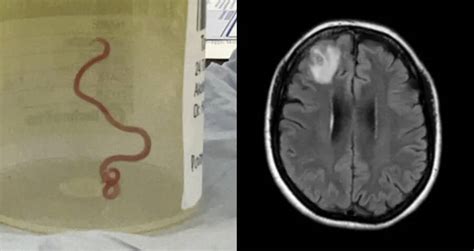

Doctors Found A Three-Inch Worm Living In A Woman's Brain

900×477

allthatsinteresting.com

www.cbc.ca > Rod McGuirk

Neurosurgeon plucks live worm from woman's brain after months of mysterious symptoms | CBC News

www.nytimes.com

She Was Depressed and Forgetful. It Was the Worm in Her Brain. - Th…

gold1017.com.au

Doctors Find 8-Centimetre Worm in Aussie Woman’s Brain

inews.co.uk

How a living, moving worm was found in an Australian woman's brain